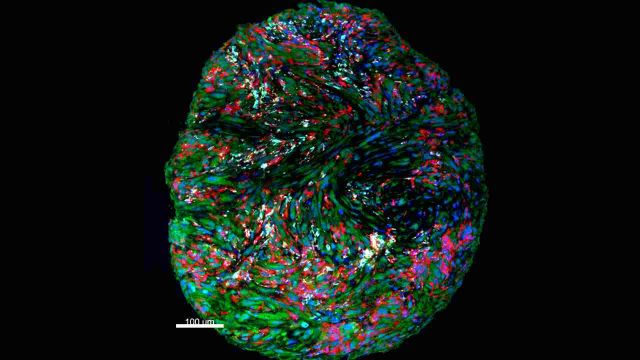

Imagen de microscopía multicolor de los componentes del sistema inmunitario tras el tratamiento de inmunoterapia Sinc

Los investigadores analizaron los cambios en el microambiente inmune del tumor antes y después de la administración de nivolumab, aprovechando las muestras quirúrgicas. Asimismo lo compararon con el tejido tumoral de pacientes que no habían recibido nivolumab. “Mediante múltiples análisis moleculares y celulares comprobamos que la administración del fármaco de inmunoterapia produce un efecto inmunomodulador local. Además, en dos pacientes, que recibieron el tratamiento antes y después de su primera intervención quirúrgica, la enfermedad no ha reaparecido tras dos años y medio de seguimiento”, confirma Melero.